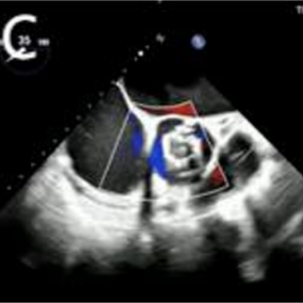

该患者为83岁男性,11年前植入的主动脉瓣(圣犹达医疗21mm)和二尖瓣(圣犹达医疗27mm)生物假体退化,导致充血性心力衰竭,左心室射血分数(LVEF)为40%,合并重度主动脉瓣狭窄/关闭不全及重度二尖瓣关闭不全。症状包括不明原因的胸闷、喘息、端坐呼吸和持续的夜间阵发性呼吸困难。检查发现心律失常、频繁早搏,二尖瓣/主动脉瓣区可闻及4/6级收缩期杂音。经胸/经食道超声心动图(TTE/TEE)确认二尖瓣生物假体重度反流[缩流宽度(VCW)8mm,平均跨瓣压差8mmHg],主动脉瓣生物假体重度狭窄/反流(平均跨瓣压差44mmHg;峰值流速5.7m/s,缩流宽度8mm)(图1)。其他检查发现左心房明显扩大,LVEF40%,中度肺动脉高压(估测收缩压57mmHg)。冠状动脉造影未见明显异常。术前心脏计算机断层扫描测量主动脉瓣环尺寸为周长58.6mm,面积252.9mm²,直径18.1mm,并发现右冠状动脉高度偏低(6.4mm)。二尖瓣瓣环直径24mm,主动脉-二尖瓣角度为61.8°,计算新左心室流出道面积为999.9mm²,提示经导管二尖瓣瓣中瓣(TMViV)术后左心室流出道梗阻风险较低。NT-proBNP显著升高(11363.03pg/mL)。由于患者高龄、既往胸骨切开术和合并症,传统再次主动脉瓣置换(AVR)或二尖瓣置换(MVR)风险过高。多学科团队在获得患者知情同意后,决定采用ScienCrown自膨式瓣膜同期进行经心尖主动脉瓣瓣中瓣(TAViV)及二尖瓣瓣中瓣(TMViV)植入术。

图1. 生物瓣膜假体功能的超声心动图评估。A:主动脉瓣生物假体严重狭窄伴反流(平均压差44mmHg;峰值流速5.7m/s ,VCW 8mm )。B:二尖瓣生物假体严重反流(VCW 8mm ,平均压差8mmHg)。